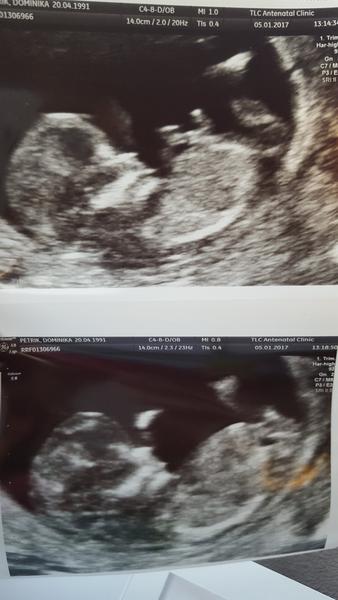

23.2. mame druhe sono, a uz sa dozvieme aj pohlavie.. nemozem sa dockat.. no a to prve sono to bolo cisto ako zazrak.. slzicky a neopistaelny pocit, ze som toho drobceka videla.. zrazu to pre mna nabralo uplne iny rozmer.. ono tam naozaj je, zije, bije mu srdiecko.. prekrasny pocit.. myslim ze kazda tehulka alebo mamicka asi vie o com rozpravam.. na to sa neda zabudnut ked prvykrat uvidite svoje babatko.. 🙂 a inac dobre.. 🙂 cim vo vyssom tyzdni som, tym sa citim stastnejsia a vdacnejsia.. 🙂 takze si to zacinam naplno vychutnavat.. momentalne 14tt+5 myslim.. dakujem inac za opytanie.. ty sa ako mas?? 🙂 pripajam fotocku zo sona.. 🙂